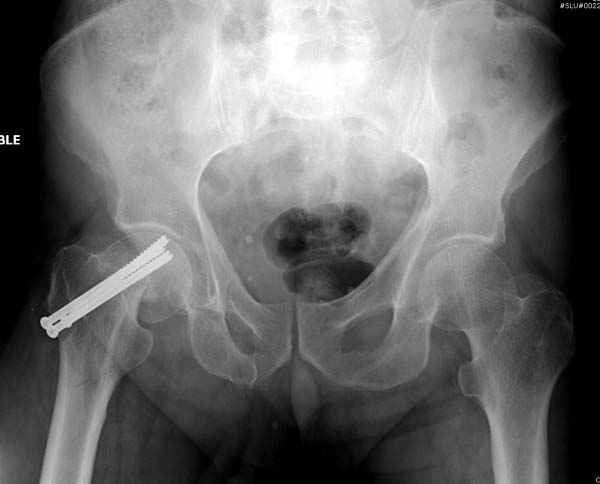

На второй день после выписки упал дома. Снимки приложены. Коллеги рекомендуют удаление шурупа и вытяжение. Что делать?

Привет из солнечного Будапешта с Eurotrauma-2008. Да, замечательный пример. Получается, профилактику расхождения отломков шейки надо было проводить каким-то реконструкционным или проксимальным гвоздем, причем сразу длинной версией. Сейчас, наверно, так и надо бы сделать.

Убрать винты, каким-то джойстиком в вертельной области сделать репозицию шейки, фиксировать ее спицами, а дальше вправлять и фиксировать как вертельный перелом.

Решайте проблемы по мере поступления. На первом этапе решение одно, и на мой взгляд верное. Ситуация изменилась кардинально - другое решение. Я бы избрал ресинтез, убрав винты заменил на Гамму. Что с ним будет послезавтра? - Будем решать послезавтра. Такая наша доля.

"Решайте проблемы по мере поступления. На первом этапе решение одно, и на мой взгляд верное. Ситуация изменилась кардинально - другое решение. Я бы избрал ресинтез, убрав винты заменил на Гамму. Что с ним будет послезавтра? - Будем решать послезавтра. Такая наша доля."

Правильно, ситуация изменилась, как говорят у нас теперь "different animal", надо решать проблему подвертельного перелома. При наличии различных вариантов фиксаторов, включая Страйкер Гамма 3, мы выбрали DePuy Antegrade Trachanteric Nail из-за многовариантности проксимальной фиксации и двойного изгиба. Вводится через вертел под 8 градусным углом, и есть достаточный передний диафизарный изгиб, предупреждающий пенетрацию дистального переднего кортекса.

Кто знает что дальше, мысленно готовы к проксимальной артропластике.

Но ведь и головка бедра сползла в варус - отчего ограничились только фиксацией подвертельного перелома, а не убрали винты и не сделали репозицию шейки?